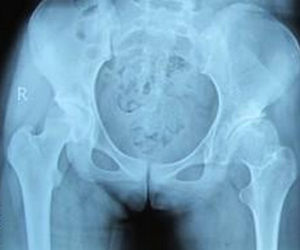

3.X檢查

更適合6個月以上者,不建議對3個月以內者進行X線檢查。拍攝髖關節正位片要求患兒安靜,下肢與肩同寬,腳尖向內鏇轉20°左右。DDH患兒的X線表現有髖臼指數增大、沈通氏線中斷、正常股骨頭骨化中心不位於由Hilgenreiner和Perkins線所構成方格的內下1/4象限內。髖臼指數隨年齡的增大而變小,2歲時應該在24°以內。小於8歲兒童,髖臼指數是測量髖臼發育的可靠指標。當患兒大於5歲,測量CE角的價值大,在成人患者,則是最有用的指標之一。當Y形軟骨閉合後,Sharp髖臼角也是測量髖臼發育不良的有用指標。

發育性髖關節發育不良正常髖關節

發育性髖關節發育不良雙側髖關節脫位